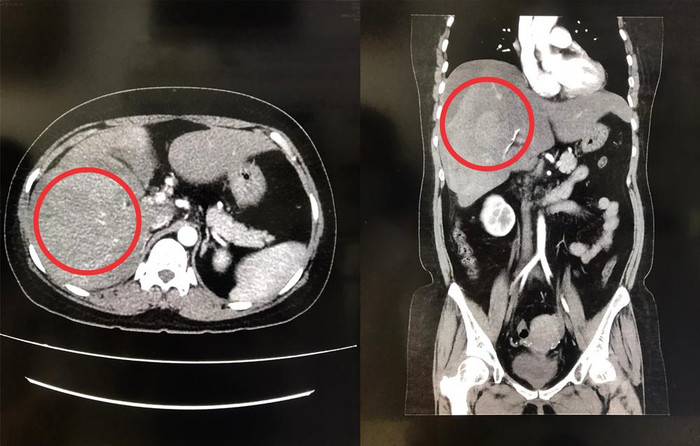

Ảnh chụp CT-scan cho thấy gan phải bị vỡ. (Ảnh: BVCC).

Đến rạng sáng 20/2, chị L. bất ngờ bị đau bụng dữ dội nên được người nhà đưa đến bệnh viện để điều trị. Qua thăm khám, bác sĩ chẩn đoán chị L. bị dập vỡ gan phải hạ phân thùy V, chảy máu ổ bụng, gây xuất huyết nội rất nguy hiểm.